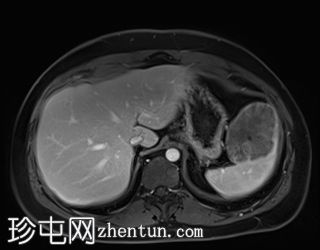

轴位

T2加权像

T1低信号,T2低信号为主的脾脏肿块,内部可见T2高信号分隔,呈进行性强化。肿块中央可见星状瘢痕。

脾脏硬化性血管瘤样结节性转化(SANT),9.8 cm肿块

顾名思义,脾脏硬化性血管瘤样结节性转化(SANT)是一种纤维性血管病变。本病例展示了SANT的一些典型影像学特征,包括边界清晰的病灶,中央可见瘢痕,以及呈放射状进行性强化。这些特征使得术前MRI诊断较为明确。尽管SANT是一种良性病变,但大多数患者仍需行脾切除术以明确病理诊断。